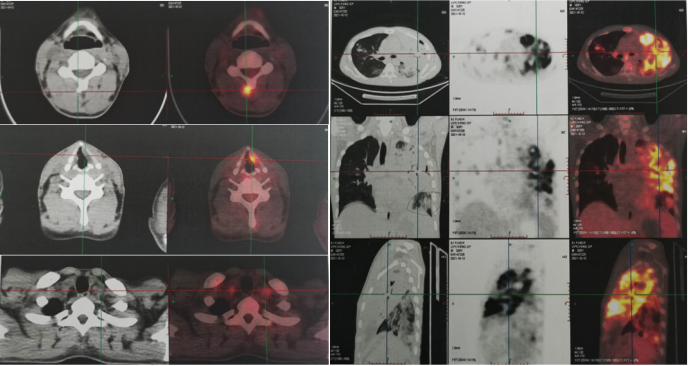

mNGS

2021年9月23日BALF mNGS回报人类疱疹病毒4型(特异序列数3)、烟曲霉(特异序列数108)、耶氏肺孢子菌(特异序列数13)。2021年9月23日血 mNGS回报人类疱疹病毒4型(特异序列数2)、烟曲霉(特异序列数20)。

患者在伏立康唑及卡泊芬净联合治疗的情况下,仍然出现影像学进展,考虑治疗效果不佳。从病原学相关因素、宿主相关因素、药物相关因素等三方面进一步明确治疗效果不佳原因。

首先进一步明确病原学,排除其他感染可能,于2021年10月15日予行肺穿刺。